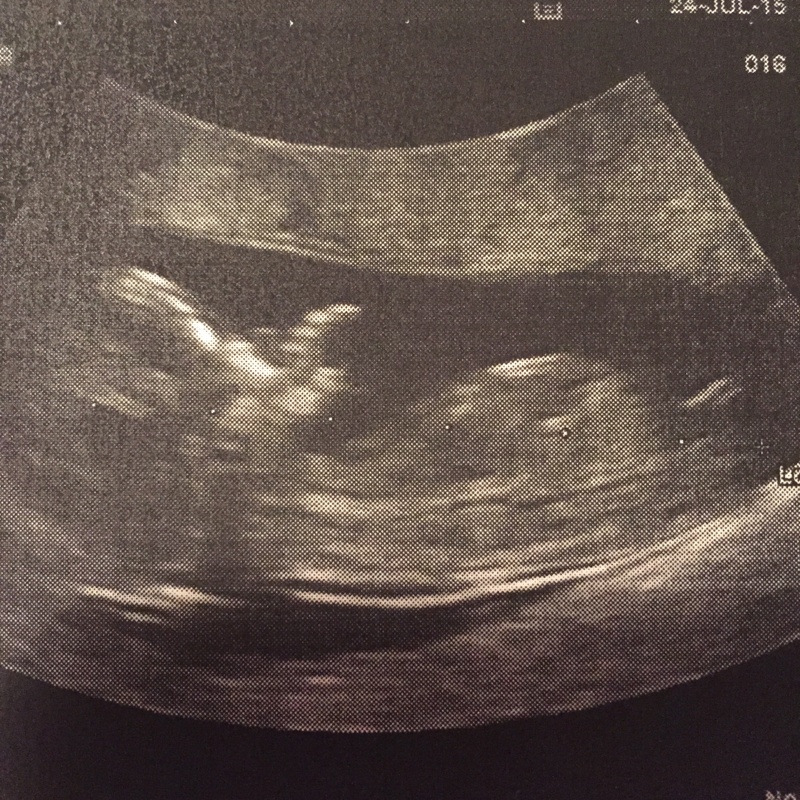

Moi j'essaie de regarder le bourgeon mais je sais pas troo si on le voit

Pièces jointes

• image-115842939.jpg

image-115842939.jpg

336.9 KB · Affichages: 68

Bourgeon fille pour le moment :-)

Cest le petit trait qu'on voit tt à droite